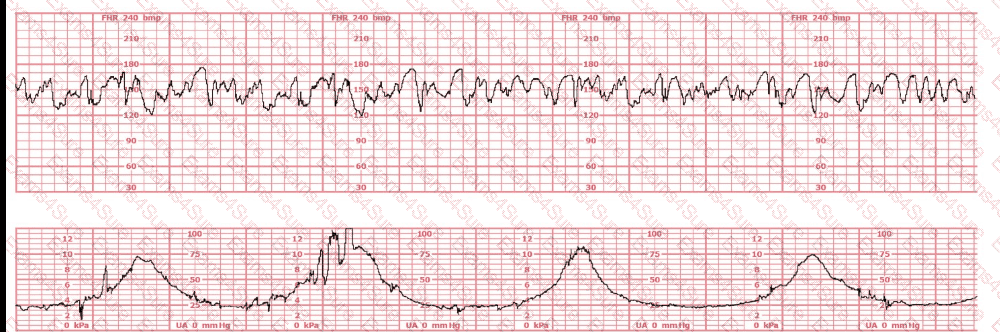

When accelerations precede a variable deceleration pattern, this is caused by

(Full question)